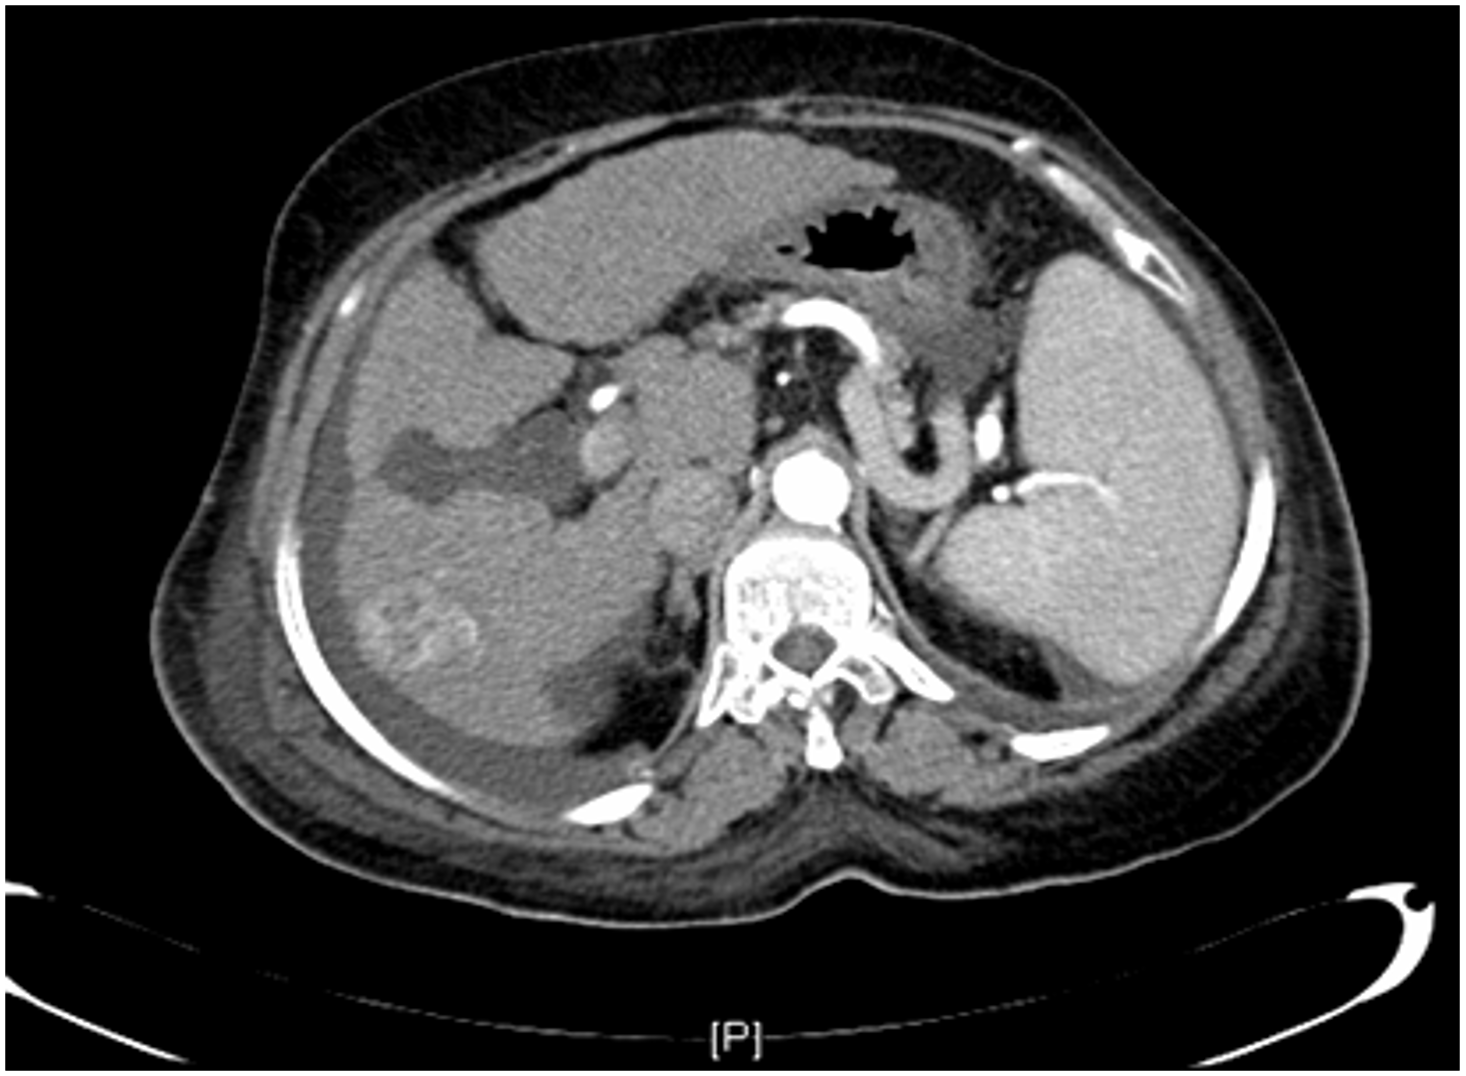

Imaging: Ultrasound, CT scan and MRI can assess the site, size, diagnosis of the tumor and can help in planning the surgical resection. CT scan will show hypervascular tumor.

HCC CT FINDINGS

Arterial phase shows hypervascularity of the HCC tumor on right lobe - washing in

in venous its opposite - washing out

diagnostic for HCC gold standard- doesnt need biopsy

irregular margin, liver shrink, ascites present

CT scan : Huge hepatocellular carcinoma in the right lobe of the liver

Huge hepatocellular carcinoma in the right lobe of the liver